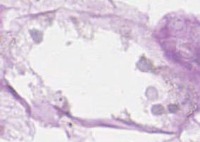

Medical Research and Diagnosis: Julio can be used by scientists and medical professionals to analyze and categorize different types of nuclei in cell samples. This can aid in diagnosing diseases such as cancer, identifying the stage of the disease, and monitoring treatment progress.

Drug Development and Testing: Pharmaceutical companies can utilize Julio to analyze and classify nuclei responses to drug treatments. By identifying the changes in nuclei structures, researchers can better understand drug effectiveness and potential side effects on cellular level.

Education and Training: The Julio model can be used as an educational tool for students and professionals in cellular biology, histology, and related fields. It can help them learn how to identify various nuclei structures and understand their functions in cells.

Digital Pathology and Remote Consultations: Julio can be integrated into digital pathology systems, helping pathologists to identify and analyze nuclei structures in medical images more quickly and accurately. Additionally, it can be utilized in remote consultations, where specialists can analyze and interpret medical images from different locations.

Automated Image Analysis in Cell Culture Monitoring: Julio can be employed to monitor cell cultures in real-time, providing valuable insights into the health and development of cell populations. By identifying and classifying nuclei, it can help researchers track cell growth, division, and death, enabling better control over experimental conditions and more accurate data collection.